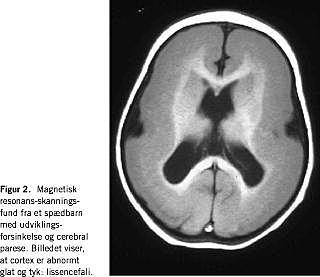

Ved lissencefali, hvor cortex cerebri er glat og tyk, ses CP, svær udviklingsforsinkelse og epilepsi (Figur 2 ). Vi vil her beskrive de fire lissencefalisyndromer, hvor CP er en tydelig del af det kliniske billede: isoleret lissencefalisyndrom (ILS), Miller-Dieker-syndrom (MDS) samt Norman-Roberts syndrom (NRS) med ledsagende ansigtsdysmorfologi og X-bundet lissencefali (XLIS).